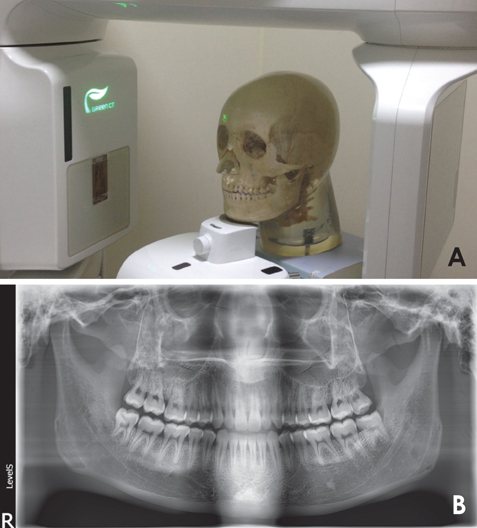

牙科细节头部模型专用于牙科X线设备而设计,如:全景牙科,头颌面摄影,牙科锥束CT,或一般三维成像应用

模型具有一个真正的人类头盖骨与下颌骨及五节颈椎,颌骨略微张开。 由于齿列完整的嵌入到组织等效材料中,因此体模不能与用于训练或测试的口腔内传感器一起使用。

适用于全景牙科,头颌面摄影,牙科锥束CT,三维成像应用模型

B.法兰克福标准平面-全景牙科摄片

人类头盖骨与下颌骨及五节颈椎